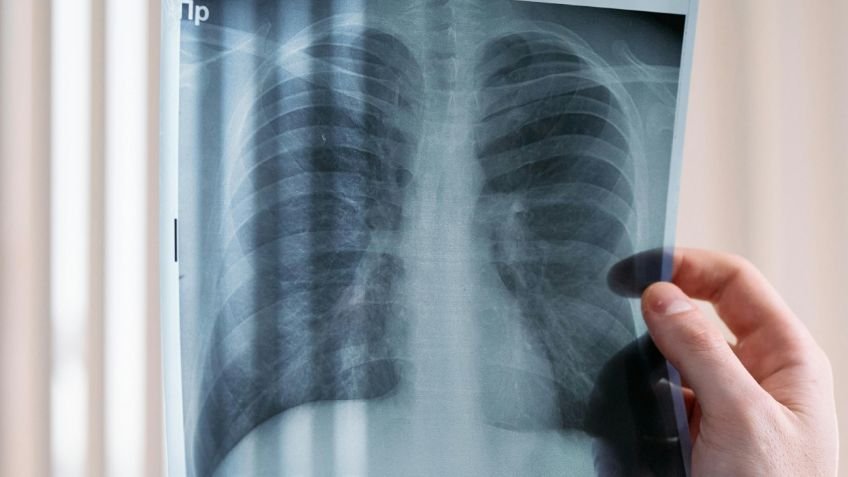

El doctor José Corona Cruz, jefe de cirugía de tórax del Instituto Nacional de Cancerología (INCan), alertó sobre el cáncer de pulmón como la segunda causa de cáncer en el mundo y la primera causa de mortalidad por cáncer a nivel global. El especialista enfatizó que esta enfermedad no es exclusiva de los fumadores, destacando otros factores de riesgo significativos y la importancia de la prevención.

El especialista detalló que, históricamente, el cáncer de pulmón era una rareza antes del tabaquismo. La inhalación prolongada de partículas cancerígenas presentes en el tabaco y los combustibles sólidos provoca alteraciones inflamatorias y genéticas que culminan en la formación de tumores malignos. Un desafío crucial en la lucha contra esta enfermedad es la ausencia de síntomas en sus etapas iniciales.

Esta característica contribuye a que este mal sea tan letal, ya que se diagnostica en etapas tardías. Los síntomas más comunes, como tos, dolor torácico y sensación de falta de aire, son inespecíficos y pueden confundirse con otras afecciones.